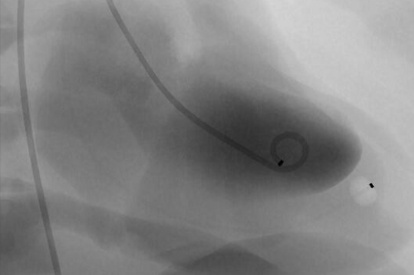

The ANGIO Mentor simulator is an essential tool for clinicians to practice and acquire the skills needed for performing endovascular interventions. Trusted by medical associations, hospitals, training centers, and the medical device industry globally, it provides trainees with realistic clinical settings to practice endovascular interventions using fluoroscopic and ultrasound guidance.

Offers true-to-life simulation of the clinical environment, including advanced imaging modalities like fluoroscopy/echocardiography, hemodynamic monitoring, medications, and interventional devices

Proven as a highly validated and effective simulator, with 30+ studies showcasing its effectiveness